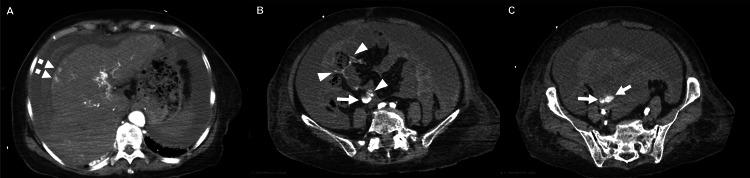

Ectopic varices represent dilated portosystemic collaterals located outside the gastroesophageal region. Although typically asymptomatic and not requiring treatment, these varices can infrequently precipitate life-threatening intraperitoneal hemorrhage. We describe a case of intra-abdominal hemorrhage caused by rupture of a superior mesenteric vein (SMV) varix due to portal hypertension. An 84-year-old Japanese woman with end-stage hepatocellular carcinoma presented to our emergency department (ED) following a transient loss of consciousness. On arrival, her vital signs were stable despite a slightly distended abdomen. While awaiting diagnostic imaging, she suddenly went into shock. Repeat bedside ultrasonography revealed increased ascites compared with the initial evaluation, accompanied by progressive anemia and worsening metabolic acidosis. Resuscitation was initiated with type O packed red blood cell transfusion and resuscitative endovascular balloon occlusion of the aorta. She was then transferred to the computed tomography (CT) room in the ED, where resuscitative procedures were continued. Contrast-enhanced CT demonstrated massive hemorrhagic ascites and extravasation around the SMV. Although both interventional radiology and surgical intervention were considered, further invasive procedures were withheld given the patient's condition and her family's wishes. Cardiopulmonary arrest occurred two hours after the collapse. Management of intraperitoneal hemorrhage from ectopic varices in the ED remains a significant clinical challenge. Emergency physicians should consider this rare etiology in patients with prolonged portal hypertension. Interventional radiology, such as transjugular intrahepatic portosystemic shunt combined with embolization, may represent a viable treatment option.

异位静脉曲张是指位于胃食管区域以外的扩张的门体静脉侧支循环。虽然这些静脉曲张通常无症状且无需治疗,但偶尔可导致危及生命的腹腔内出血。我们报告一例因门静脉高压导致肠系膜上静脉(SMV)静脉曲张破裂引起的腹腔内出血病例。一名84岁的日本女性终末期肝细胞癌患者,在短暂意识丧失后被送往我们的急诊科(ED)。到达时,尽管腹部稍有膨隆,但其生命体征稳定。在等待诊断性影像学检查时,她突然休克。与初次评估相比,重复床边超声检查显示腹水增加,伴有进行性贫血和代谢性酸中毒加重。开始进行O型浓缩红细胞输血和主动脉复苏性血管内球囊闭塞术进行复苏。然后她被转移到急诊科的计算机断层扫描(CT)室,在那里继续进行复苏程序。增强CT显示大量出血性腹水和SMV周围的造影剂外渗。尽管考虑了介入放射学和手术干预,但鉴于患者的病情和家属的意愿,未进行进一步的侵入性操作。晕倒两小时后发生心跳骤停。急诊科对异位静脉曲张引起的腹腔内出血的处理仍然是一项重大的临床挑战。对于门静脉高压持续时间较长的患者,急诊医生应考虑这种罕见的病因。介入放射学,如经颈静脉肝内门体分流术联合栓塞术,可能是一种可行的治疗选择。